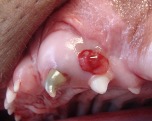

Abbildung 6: Persistierende Unterkiefermilchzähne, die bleibenden

Eckzähne stossen zu weit innen.